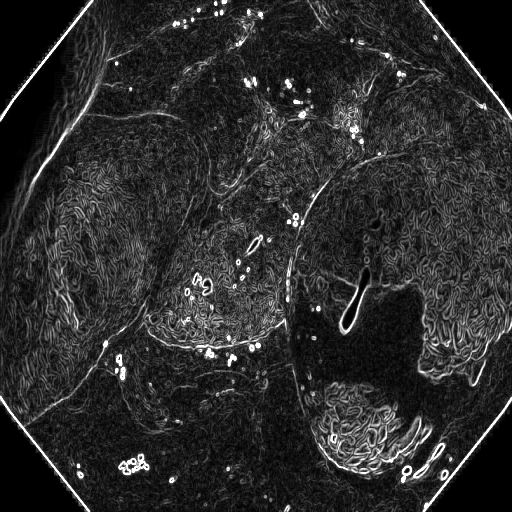

The Edge-Guided Feature Enrichment (EGFE) unit actively enhances feature representation by integrating edge knowledge into the set of features. It applies a Sobel operator to the input feature set, generating separate gradient magnitude maps for horizontal and vertical directions (Fig. 3). As illustrated in Fig. 3, the Sobel operation in a single direction captures limited information about the polyp. However, combining these maps (Fig. 3(d) and Fig. 3(h)) effectively captures polyp boundaries and enriches learned features. The final gradient magnitude map, produced using the Euclidean norm (Eq. 1), highlights regions with significant intensity changes at polyp boundaries.

where , , and denotes 2D Sobel operation, ReLU activation function, the number of 2D convolutions with respectively, and represents the edge-guided features learned at the -th layer. This element-wise addition facilitates the fusion of edge information extracted by the Sobel operator with the spatial features learned by the convolutional layers. This fusion enables the framework to focus on and refine the representation of polyps, ultimately contributing to enhanced segmentation performance.

Fig. 7 offers qualitative validation, showcasing MNet-SAt’s superior polyp mask generation compared to baselines across four cases. This qualitative superiority aligns with the previously established quantitative results. In the case of small polyps (first and fifth rows), all baseline methods initially appear to produce satisfactory visual results. However, upon closer inspection, they fail to maintain fine boundary details. Our framework excels in preserving polyp anatomy and topology for medium and large polyps, significantly outperforming the baseline methods. Notably, even in multiple polyps, our framework successfully captures more polyps and approximates the ground truth more closely. The primary reason for this superior performance is the EGFE module, which effectively eliminates noise in conjunction with the HMAtt module, resulting in a few false positives. Our analysis reinforces MNet-SAt’s effectiveness in handling challenging polyp scenarios (small, medium, large-scale, and multi-polyps) while suppressing non-regions of interest.